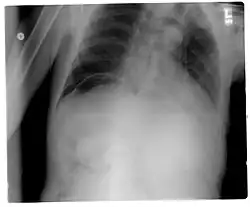

Un pneumopéritoine de faible volume est le plus souvent asymptomatique. Il est avant tout suspecté dans un contexte clinique. La radiographie (abdomen sans préparation (ASP) et/ou cliché debout de face, centré sur les coupoles diaphragmatiques) permet généralement de faire le diagnostic, le pneumopéritoine apparaissant comme un croissant radio transparent sous-diaphragmatique, uni ou bilatéral et de taille variable[1]. Cependant, un pneumopéritoine de faible abondance peut facilement passer inaperçu a la radiographie. C'est pourquoi la tomodensitométrie (ou scanner abdominal) est aujourd'hui considérée comme l'examen de référence pour son diagnostic[2]. La tomodensitométrie permet de rendre visible des volumes aussi faibles que 5 cm3 d'air ou de gaz.